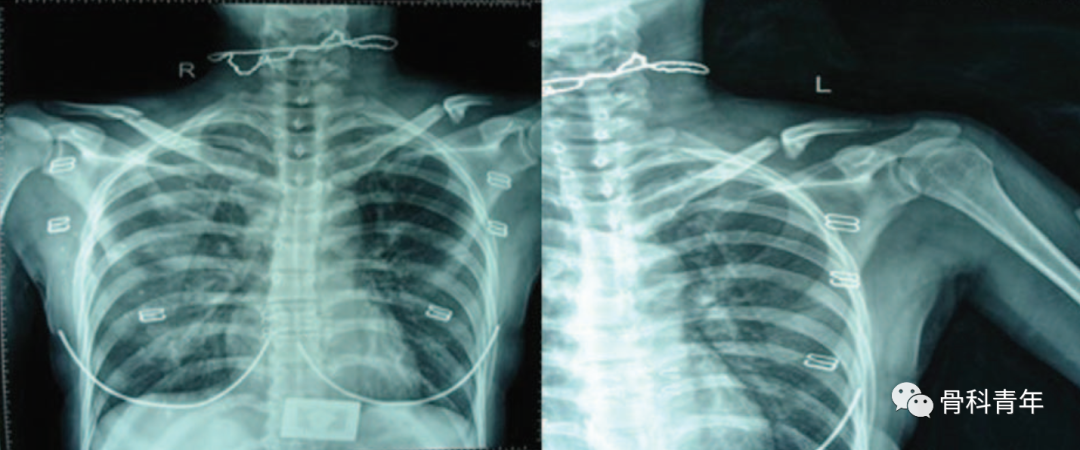

左锁骨骨折合并同侧肩锁关节脱位,采用钩钢板+锁骨钢板固定。

为此,有学者提出采用锁骨钢板+锚钉联合固定的方法,下图所示一例锁骨中段骨折合并同侧IV型肩锁关节脱位患者:

先采用锁骨解剖钢板固定锁骨骨折,复位脱位的肩锁关节后,在喙突置入两枚金属锚钉,并将锚钉自带缝线分别穿过锁骨钢板螺钉孔,在锁骨前方及后方分别打结固定,最后采用缝线直接缝合肩锁韧带及喙锁韧带: